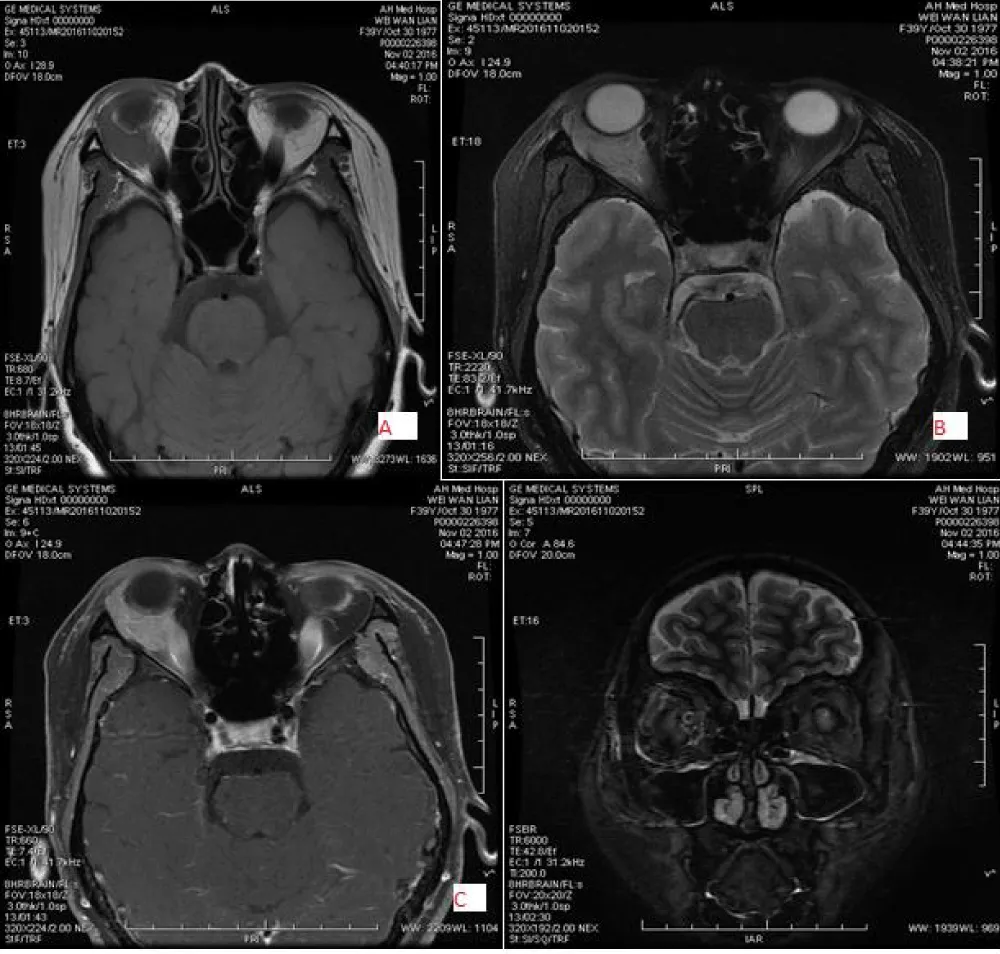

The intraconal space is located between the outside of the optic nerve and the inside of the extraocular muscle. In this space, many types of tumors may occur, but the most common tumor is cavernous hemangioma, seen in adults and capillary hemangioma in children. Cavernous hemangioma is usually present with a painless progressive mass, well-defined margin, regular shape, slightly high density, low or slightly high intensity on T1WI, high intensity on T2WI and gradual enhancement, making it easy to distinguish between the optic nerve and extraocular muscles. Orbital cavernous hemangioma and schwannoma present with slow progressive enlargement, and most of their clinical and radiological features are similar to each other [18-20]. Dynamic contrast-enhanced MRI is useful to distinguish between cavernous hemangioma and schwannoma. After Gadolinium administration in both patients cavernous hemangioma shows enhancement starting from a small point or portion and contrast media filling up the tumor, called “progressive enhancement”, while in the schwannoma, enhancement starts from a wide area and later shows heterogeneous enhancement. Other tumors that may occur in this space include schwannoma, meningioma, hemangiopericytoma, lymphoma, and metastasis (Figure 4).

Download Image

Figure 4: 44-year-old male with left-sided cavernous hemangioma, located in the intraconal and superomedial region with oval shape and well defined, low signal intensity on T1WI(A) and high signal intensity on T2WI (B) and gradual homogeneous enhancement (C&D).